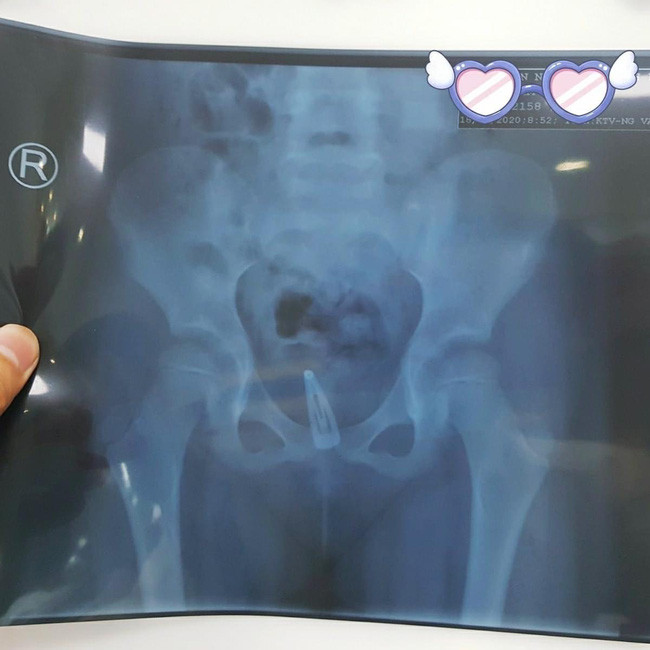

Tại bệnh viện, bé được chụp X Quang bụng không sửa soạn, thử nước tiểu, siêu âm bụng. Bác sĩ chẩn đoán Nhiễm trùng tiểu - dị vật âm đạo.

BS CK2 Huỳnh Cao Nhân, trưởng Khoa Ngoại Niệu và BS CK1 Đỗ Tiến Phát cho biết: Qua thăm khám thấy bé vùng kín bé viêm đỏ nhiều, niệu đạo có dịch mủ, âm đạo viêm đỏ có ít dịch vàng hôi. Dựa trên kết quả chụp X Quang phát hiện dị vật âm đạo, chúng tôi tiến hành nội soi gắp dị vật là cái kẹp tóc bằng kim loại đã rỉ sét do bị quá lâu nên oxy hóa, niêm mạc âm đạo viêm đỏ gần sinh mủ.

| Dị vật phát hiện qua hình ảnh chụp XQuang. |